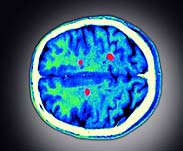

All participants underwent a brain MRI scan and specific MRI metric analysis.

The MRI measured two types of brain tissue damage—T1-lesion volume, which shows "black holes," or hypointense lesions, which are areas of permanent axonal damage; and T2-lesion volume, which shows the total number of lesions (lesion load) and overall disease burden.

Both of these measures indicated that MS is more aggressive in children in the early stages, said the researchers.